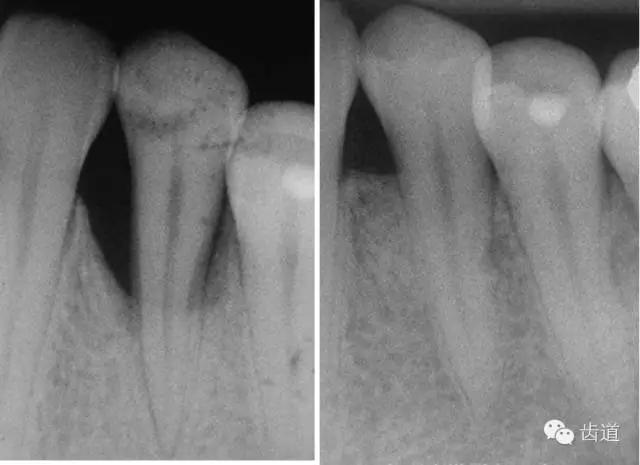

1、垂直型骨缺損:垂直性吸收形成的骨下袋,三壁袋和二壁袋的效果好,一壁袋的效果最差;

如術(shù)區(qū)患牙無(wú)咬合創(chuàng)傷;為垂直性骨吸收且在III度以?xún)?nèi);殘留骨壁數(shù)目多(三壁骨下袋);骨缺損窄而深(角度<250°,深度>3mm);牙齦組織較寬且厚度 >1mm(抗張強(qiáng)度大及血供充分)時(shí);則臨床附著水平和骨量增加顯著。另外,根據(jù)病損牙位的特征(前牙、后牙、鄰間隙、根分叉等)選擇不同形狀、大小的屏障膜也很重要。